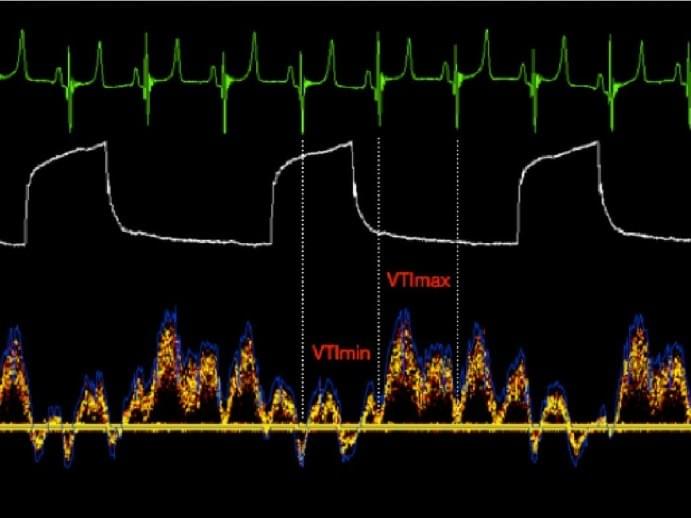

The picture shows a typical flow decrease (VTI min) during inspiration in the hypovolemic patient ventilated patient.